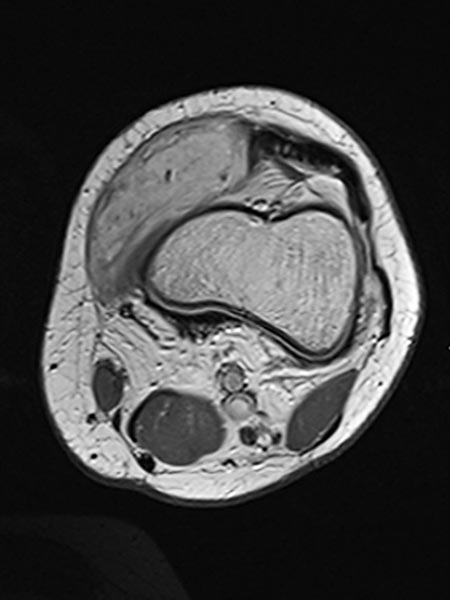

In der axialen T2-gewichteten MRT zeigt sich eine hyperintense, homogene Raumforderung im Bereich der Schwellung, gut vereinbar mit einer venösen Malformation. Auffällig einige kleinere zentrale flow-voids im Sinne von Arterien in der Läsion.